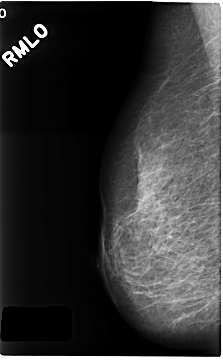

C_0216_1.RIGHT_MLO

RIGHT_MLO LINES 4680 PIXELS_PER_LINE 2888 BITS_PER_PIXEL 12 RESOLUTION 50 NON_OVERLAY